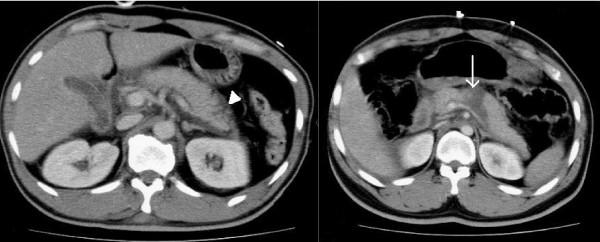

To assess the efficacy of computed tomography (CT) in evaluating patients with pancreatic trauma.

We undertook a retrospective review of all blunt trauma patients admitted to the Chi-Mei Medical Center from January 2004 to June 2006. Every patients underwent abdominal CT scan in emergency department and the CT scans were obtained with a four-slice helical CT. Diagnosis of a pancreatic injury in these patients was by surgical observation or by CT findings. Radiographic pancreatic injuries were classified as deep or superficial lesions. Deep lesions were defined as the hematomas or lacerations >50% thickness of the pancreas. Superficial lesions were described as the hematomas or lacerations <50% thickness of the pancreas; pancreatic edema; and focal fluid accumulation around the pancreas

Nineteen patients with pancreatic trauma, fourteen males and five females, average age 40.6 ± 21.4 years, were included. Most patients (73.7%) with pancreatic trauma had associated organ injuries. CT was performed in all patients and laparotomy in 14 patients. CT was 78.9% sensitive in detecting pancreatic trauma. All deep pancreatic lesions revealed on CT required surgical treatment, and complication was discovered in two patients undergoing delayed surgery. Superficial lesions were managed conservatively.

Four-slice helical CT can detect most pancreatic trauma and provide practical therapeutic guidance. Delayed operation might result in complications and is associated with prolonged hospital stays.